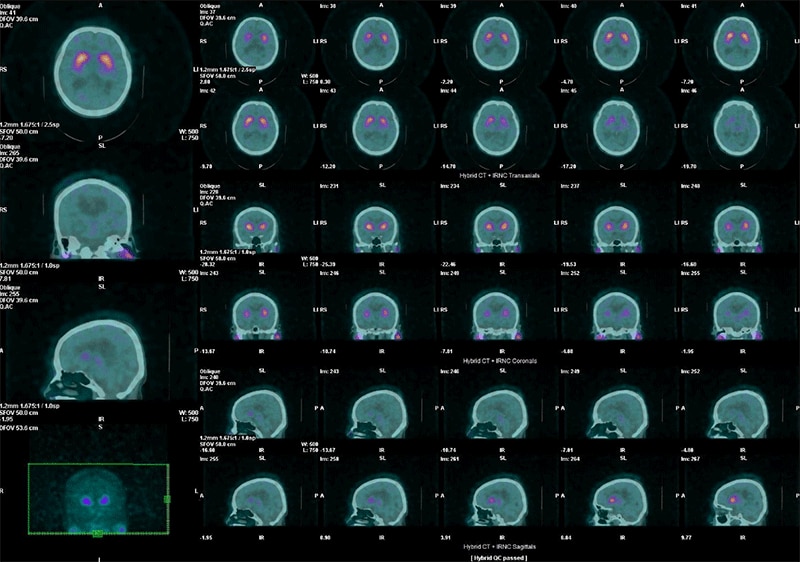

脳血流シンチでも吸収補正のためにCT撮影を行っています。従来のChang法では考慮されてないヘッドレストや頭骨による減弱も補正することができ、より正確な脳内分布が得られることが期待できます。また、ドパミントランスポーターシンチグラフィ検査ではCT画像を活用し、頭部のリフォーマット処理時にFusion画像上でCT画像を参照しながら角度調整を行っています。術者間の処理の誤差を減らすことにも、CT画像が役に立っています。

ドパミントランスポーターシンチグラフィ CT画像とのFusion